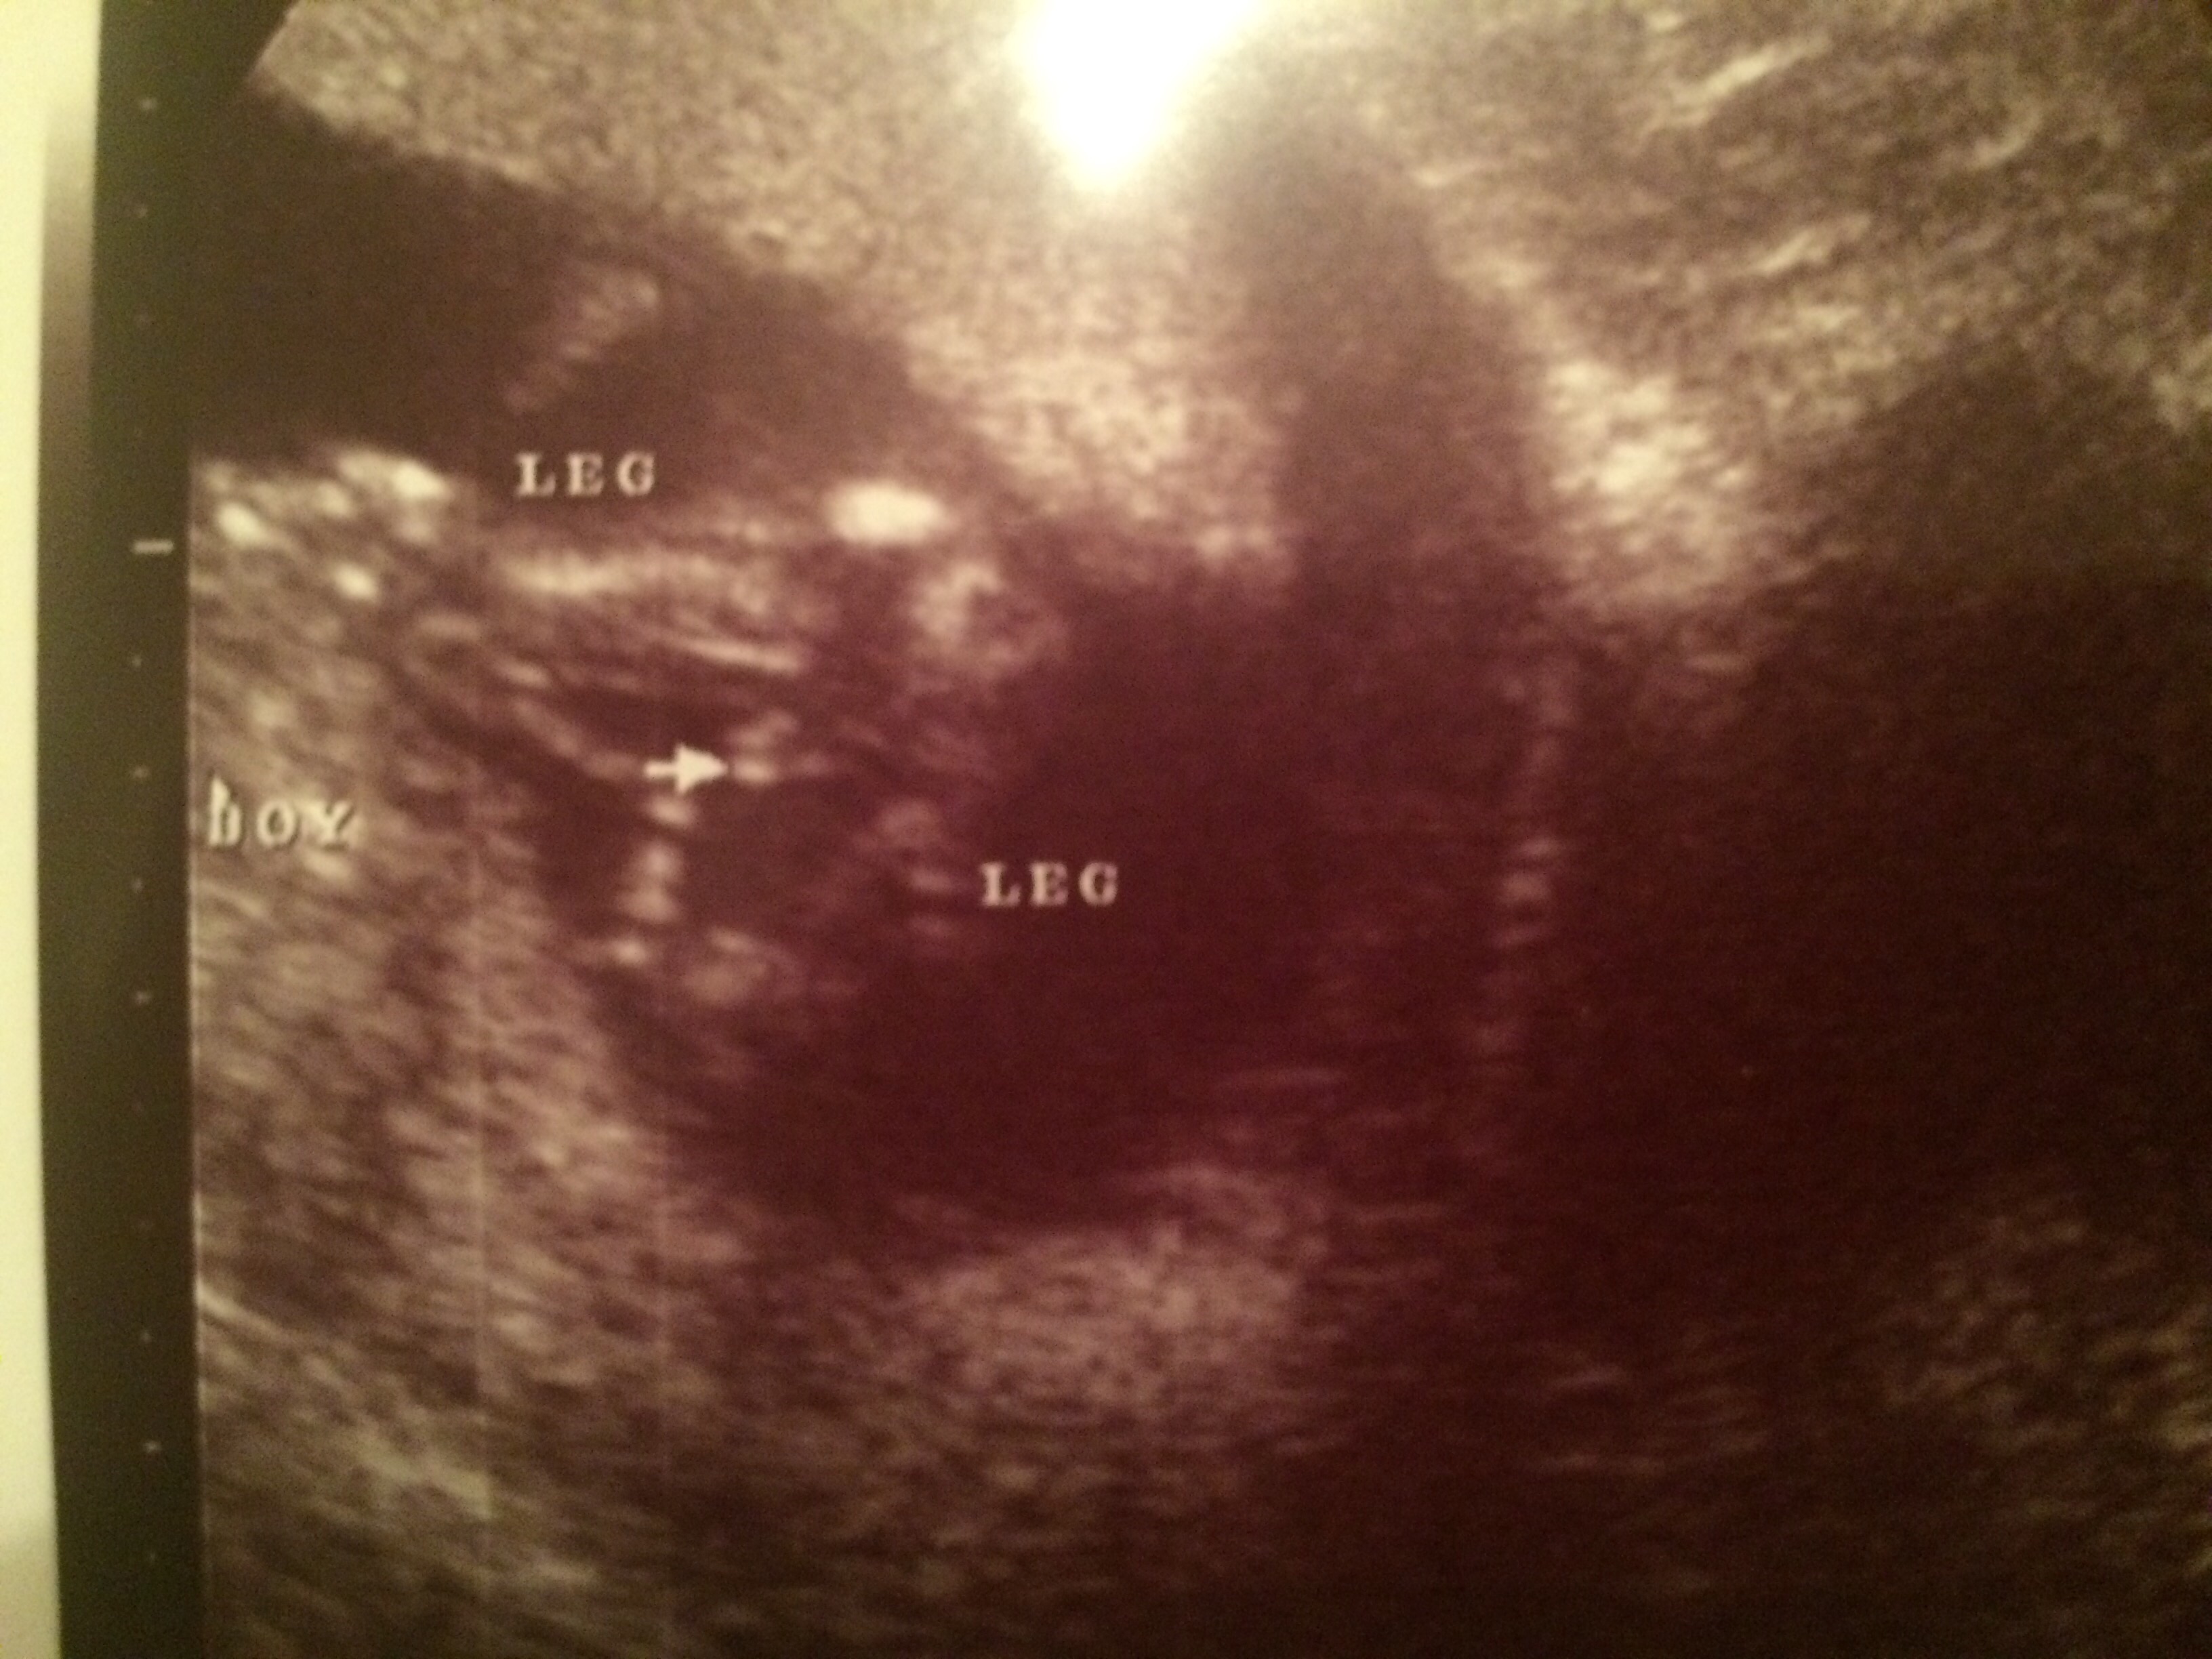

Had an ultrasound on Monday 3/2 (17 weeks 4 days), baby was very stubborn and would not uncross it's legs but my midwife thinks that we are team pink because she said she did not see anything that looked like boy parts from any of the angles. We hope to find out for sure on the 23rd at my 20 week scan as long as baby plays nice and opens it's legs!